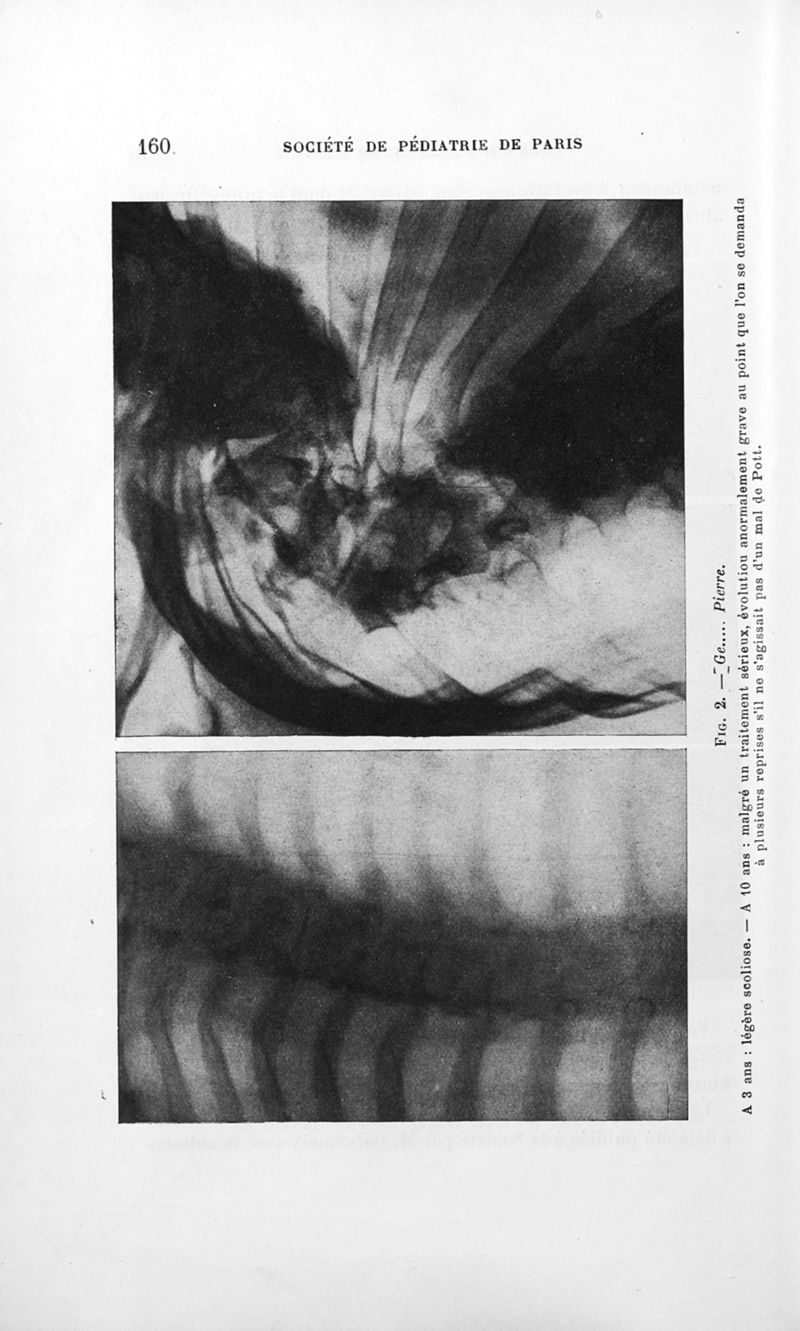

Bulletins de la société de pédiatrie de Paris

Tome trente-deuxième. - Paris : Masson et Cie, 1934.